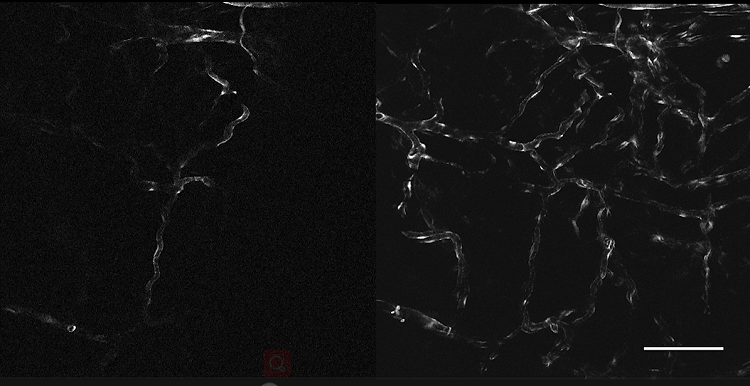

3、肿瘤血管生成OptiScan成像

左:正常皮肤微脉管系统;右:黑色素瘤影响的皮肤微脉管系统。

注:活体CLE成像显示无胸腺小鼠植入黑素瘤内及周围的黑素瘤相关脉管系统发生变化,静脉注射(0.3 ml, 10 mg / ml)fitc-葡聚糖作为造影剂。Scale bar=100μm。